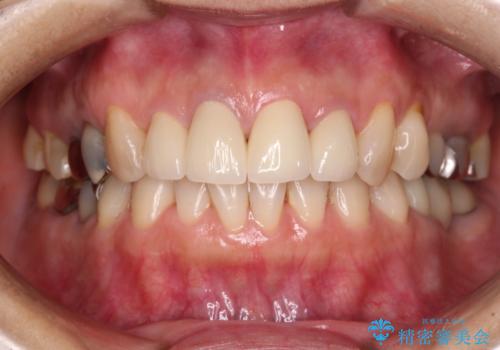

痛む奥歯と見栄えの悪い前歯 オールセラミックによる補綴治療

- 近医にて奥歯の抜歯が必要と言われたとのことで来院された患者様です。

診断の結果、奥歯は歯根が破折しており、抜歯が必要な状況でした。

インプラントあるいはブリッジによる補綴治療が考えられましたが、前後の歯が大きな銀歯であったため、オールセラミックブリッジにより3本の歯を審美的に仕上げることとしました。

前歯は神経を取り除いて変色した歯や金属の縁が見える歯などがあり審美的に気になっていましたが、治療するかどうかは悩んでいらっしゃいました。

奥歯の治療をしている間に前歯の治療をどのように勧めるのか検討していただき、最終的には4歯を一度に治療し、審美的に仕上げることとしました。